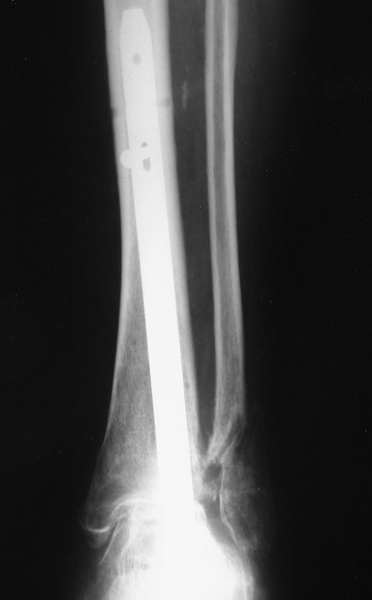

Можно: 65-летняя пациентка, оперирована по поводу несросшегося в гипсе перелома лодыжек с патологической вальгусной установкой стопы и выраженным нарушением опрной функции. Оперирована через 6 месяцев после травмы. Рентгенограммы через 4 месяца после операции.

Уважаемый А.Семенистый. Складывается впечатление, что вы выполнили трехсуставный артродез, уж больно длинные блокирующие винты. Не мешают ли они пациентке при ходьбе?

Да конечно винты длинноваты! Мешают ли ходить? Во всяком случае субьективно пациентка удовлетворена. Ходит, естевственно, хуже чеи до травмы, но намного лучше, чем до операции.